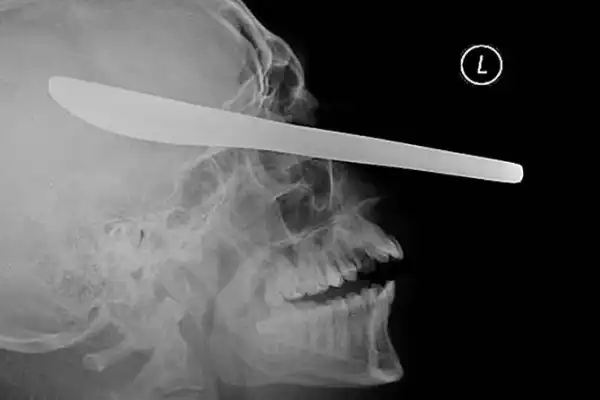

Нож в голове 10-летнего мальчика. Мальчик выжил.

12-сантиметровый нож в черепе подростка.